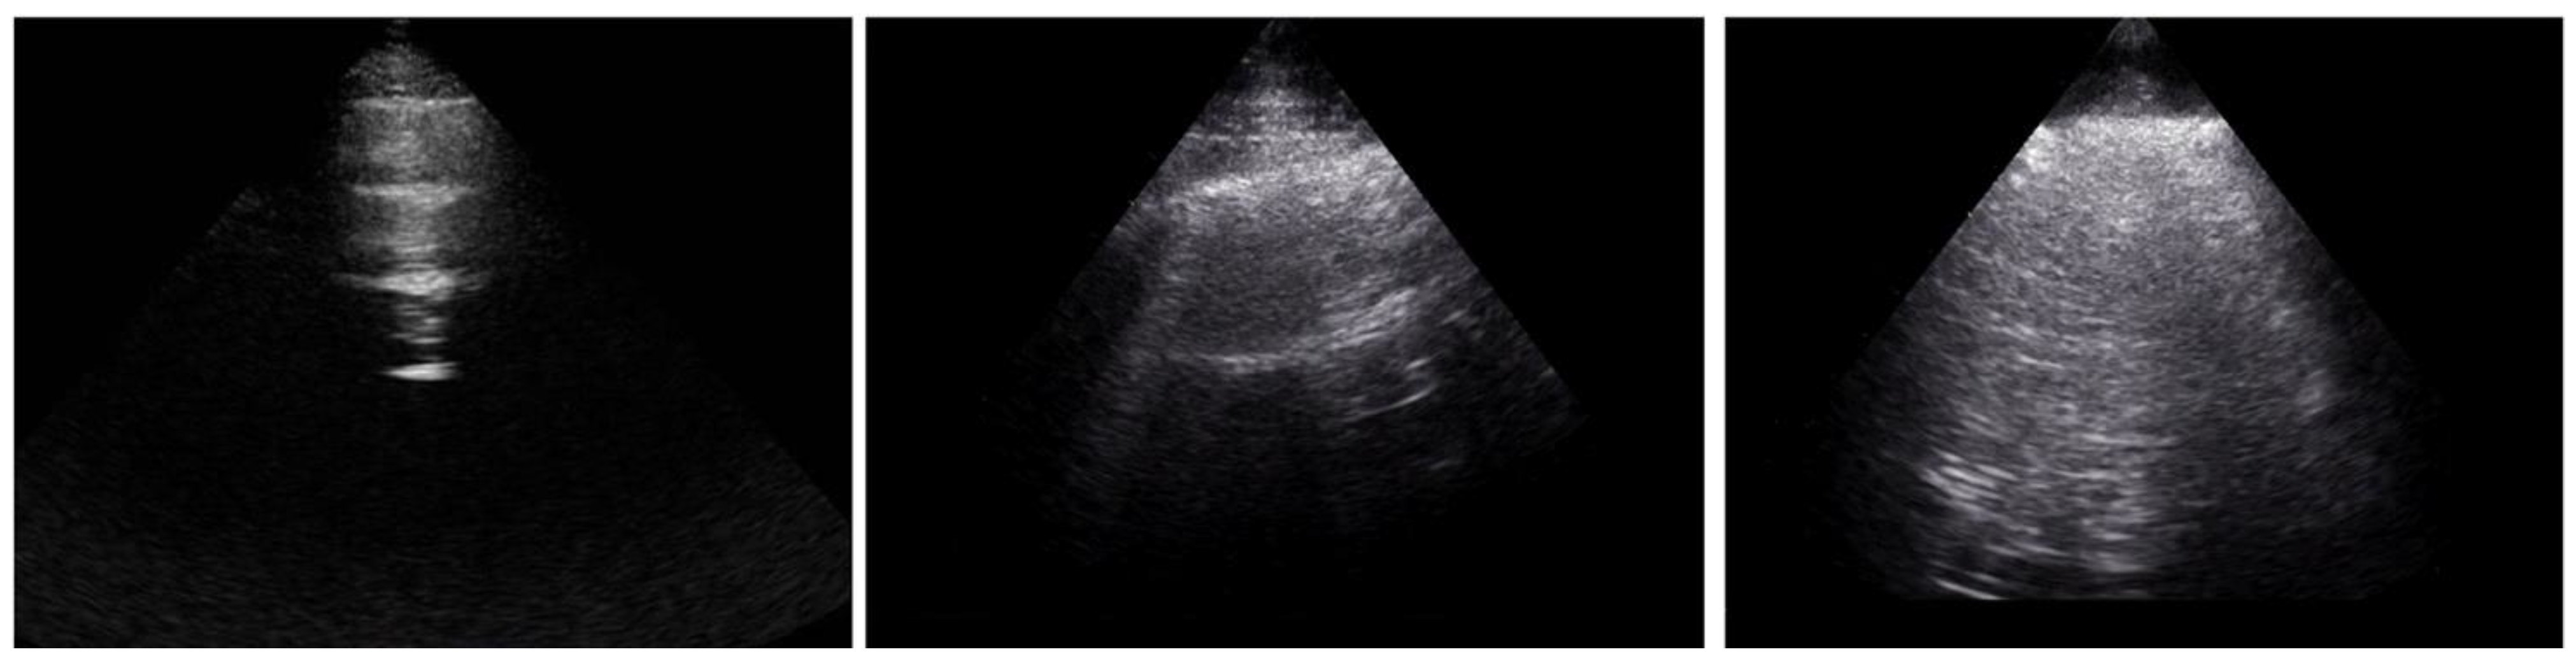

LUS is a radiation-free, non-invasive, bedside technique which has been studied in different conditions, including SSc. The number of B-lines distinguished between the presence and absence of SSc-ILD in previous publications, including early sub-clinical cases [23,24]. In addition, some authors have shown the relationship between the quantification of B-lines and the visual CT ILD extent scoring method by Warrick et al. using the Scleroderma Lung Study I scoring system, with higher numbers of B-lines in patients with higher ILD extent [18,21,22,25]. In comparison to previous reports, we confirm the correlation with the CT Wells score and the number of ultrasound B-lines, although with lower coefficients, possibly related to the use of a different number of scanning sites. In comparison to the other CT visual quantitative scoring methods, the classification into limited or extensive ILD according to the Goh et al. staging system carries prognostic implications [8]. In our population, the number of anterior B-lines distinguished limited and extensive ILD, with a trend towards statistical significance for the total B-lines count. Similarly, posterior and total B-lines significantly differentiated the presence of limited ILD from the complete absence of ILD. These results may be related to the natural history of SSc-ILD, which initially affects posterior-basal peripheral areas and progressively expands to anterior and proximal segments of the lung parenchyma, further supporting the ability of LUS to also detect early sub-clinical interstitial involvement and indicating its role in detecting a progression of ILD extent. In line with previous reports, PFT parameters (in particular DLCO% and DLCO/VA%) significantly distinguished extensive from limited ILD, although they did not differ between limited and absent ILD. Conversely, FVC% and TLC% can significantly separate extensive versus absent ILD only, confirming that they may be associated with a delay in detecting milder forms of ILD [26]. Therefore, B-lines may add information to the sole use of PFTs, in particular to support the differentiation between absent, limited and extensive ILD, providing anatomical details in a functional evaluation (Figure 4).

Figure 4. Example of systemic sclerosis patients with extensive (first-line), limited (second-line) and absent (third-line) interstitial lung disease. CT = computed tomography; DLco = diffusion lung capacity of carbon monoxide; DLco/VA = diffusion lung capacity of carbon monoxide corrected for alveolar volume; FVC = forced vital capacity; KUR = kurtosis; MLA = mean lung attenuation, measured in Hounsfield unit; SKEW = skewness; TLC = total lung capacity.